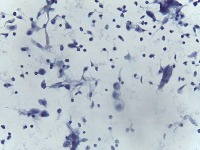

Medical Diagnostics: This model can be used in the healthcare industry to provide high-speed automated analysis of pathology slides, determining whether cells are normal or abnormal, and assisting in diagnosis of various diseases such as cancer.

Scientific Research: Researchers studying cell biology or genetics can use this AI model for their studies on cellular abnormalities and diseases. This can accelerate the onset of breakthroughs in medical science.

Pharmaceutical Applications: Pharmaceutical companies can use this model in drug discovery and development process. By identifying how different medications affect normal and abnormal cells, they can speed up and enhance their research.

Educational Tool: This AI model could serve as a rich educational tool in courses related to biology, medicine and health sciences, helping students to visualize and understand differences between normal and abnormal cells.

Personalized Medicine: This model can be used to analyze patients' cells to create personalized treatment plans. Understanding an individual's cellular structure could help healthcare professionals tailor treatments to the patient's specific needs.